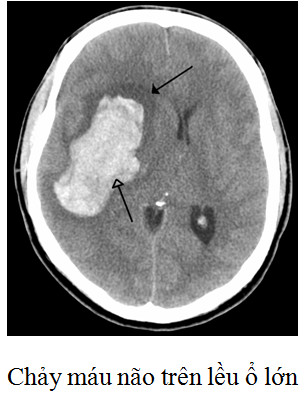

Tiên lượng kết cục chảy máu trong nhu máu não phụ thuộc rất lớn vào thể tích khối máu tụ và mức độ rối loạn ý thức, theo Broderick JP nếu điểm Glasgow < 9 và thể tích máu tụ trong não > 60 mL: 90% tử vong trong 1 tháng. Điểm Glasgow ≥ 9 và thể tích máu tụ trong não < 30 mL: 17% tử vong trong 1 tháng.

Nguyên nhân dẫn tới tiến triển xấu phần lớn do chảy máu tái phát làm khối máu tụ tiến triển gây hiệu ứng choán chỗ. Bên cạnh Hubet6677 phiên bản mới nội khoa thông thường theo phác đồ chảy máu não thì Hubet8888 lì xì hội viên mới mở sọ lấy máu tụ, giải chèn ép là một biện pháp để ngăn ngừa tử vong do hiệu ứng choán chỗ.

| Lấy bỏ khối máu tụ bằng Hubet8888 lì xì hội viên mới thường được dành cho các Tại game HUBET có kèm theo tiêu chuẩn sau (Theo Acute stroke care – Ken Uchino 2013 và Hướng dẫn Hubet6677 phiên bản mới chảy máu não trên lều Hiệp hội Đột quỵ não Hoa Kỳ 2013): - Tuổi: Không có giới hạn tuyệt đối nhưng nên dưới 75 tuổi. - Các chảy máu tiểu não có hiệu ứng choán chỗ gây: • Di lệch não thất IV. • Dãn não thất • Chèn ép thân não. • Suy giảm ý thức (nhưng không chờ đến khi Tại game HUBET bị hôn mê nếu họ có đủ các tiêu chuẩn trên). - Với chảy máu nhu mô não trên lều cân nhắc Hubet8888 lì xì hội viên mới với: • Ổ máu tụ sát bề mặt vỏ não (khoảng cách dưới 1 cm) • Thể tích > 30 mL kèm hiệu ứng choán chỗ và rối loạn ý thức. Hiện tại Trung tâm Đột quỵ phối hợp cùng khoa Phẫu thuật Thần kinh đã triển khai Hubet8888 lì xì hội viên mới mở sọ giải áp lấy máu tụ cho các Tại game HUBET chảy máu não có chỉ định. |